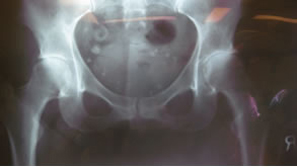

First case was a 47-year-old small female with mechanical impingement, torn labrum, and over 30% delamination of acetabular articular cartilage. There was also concern as to the sizing, that it might be too small for the size 1 ARC stem with a socket size of 46 mm.

Intra-operative x-ray helps check mechanical alignment and modular features allow for last minute fine tuning. Neck length adjusted. Stem fit like a custom implant. 2 prox x 10 mm. |